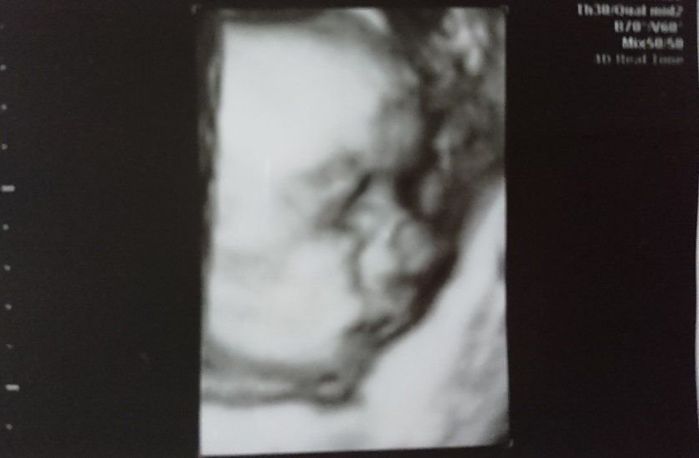

妊娠33週目のエコー写真

やっと産休に入り、体を休める事ができた幸せな時期でした。時間に余裕ができたので、少しずつ男の子の名前を考えていました。予定の帝王切開の手術まで1カ月あるので、まだ出産の準備はしていませんでした。まさか次の妊婦健診の日に産む事になるとは、夢にも思っていませんでした。赤ちゃんの推定体重は2493gでした。